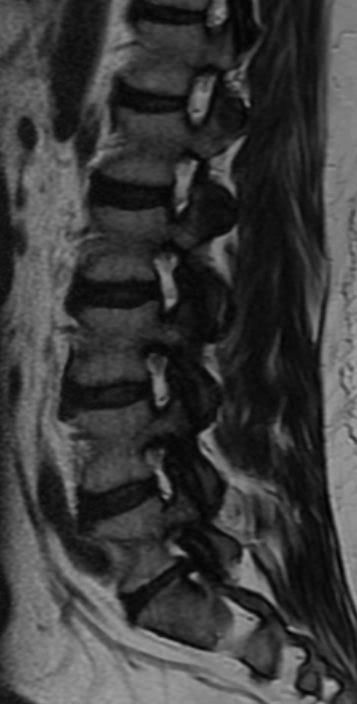

I just had an MRI done and they gave me a disk to take with me for a Doc that will be calling me.

Can anyone tell me how bad is it? Just a heads up on what can be expected.

I won't hold you to your diagnosis.